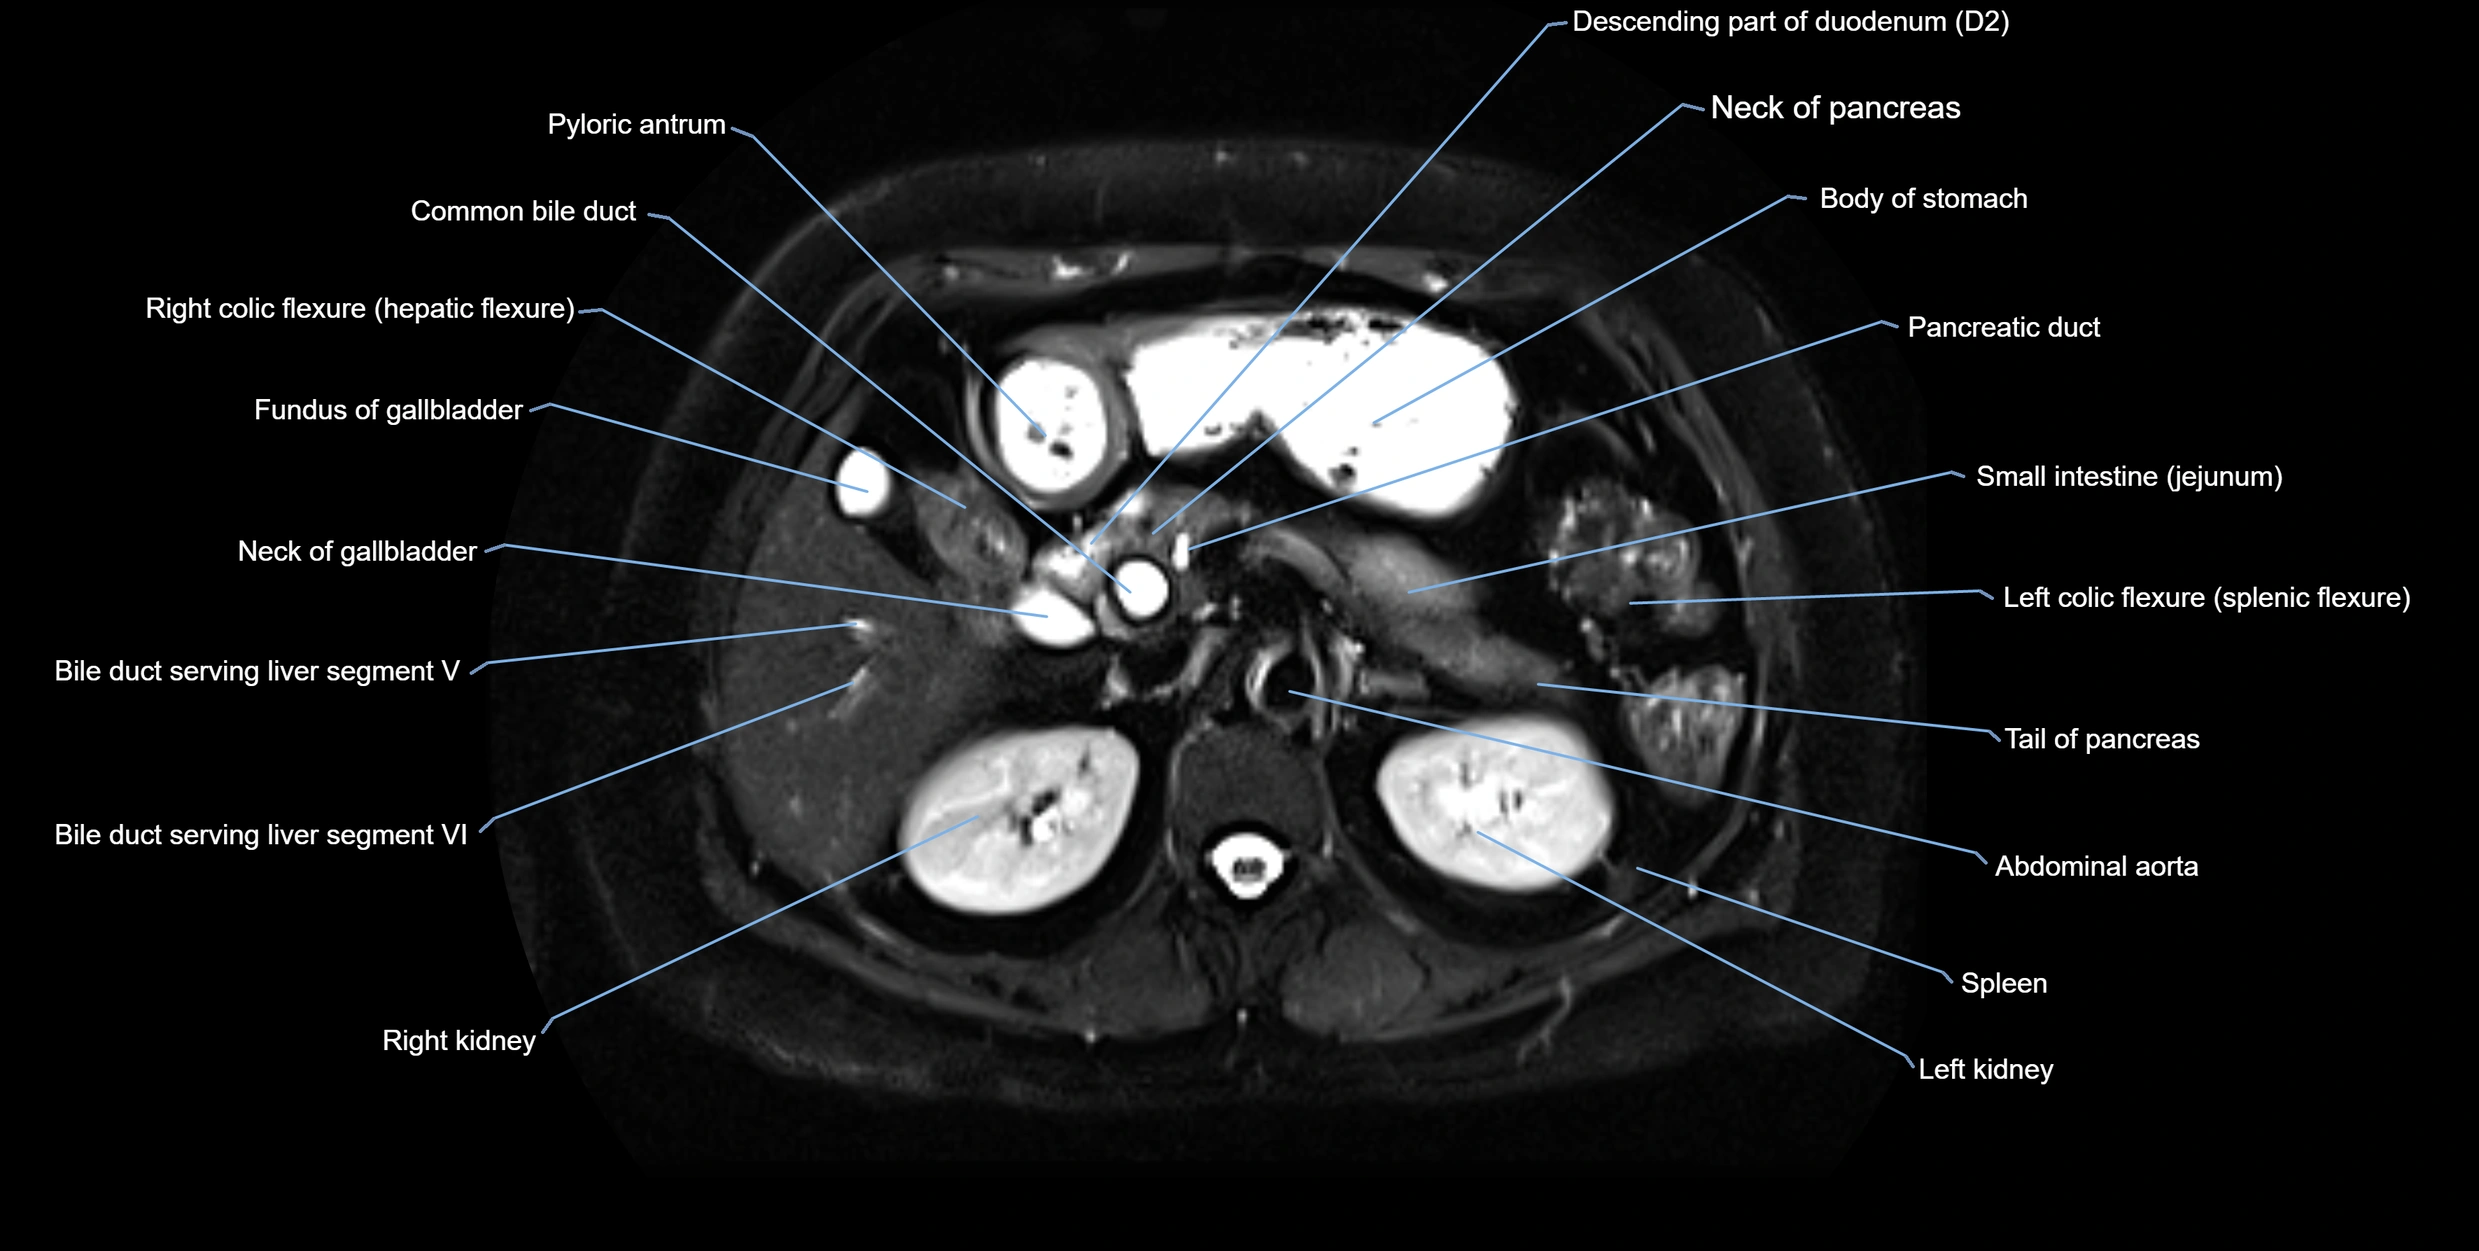

MRI image

image